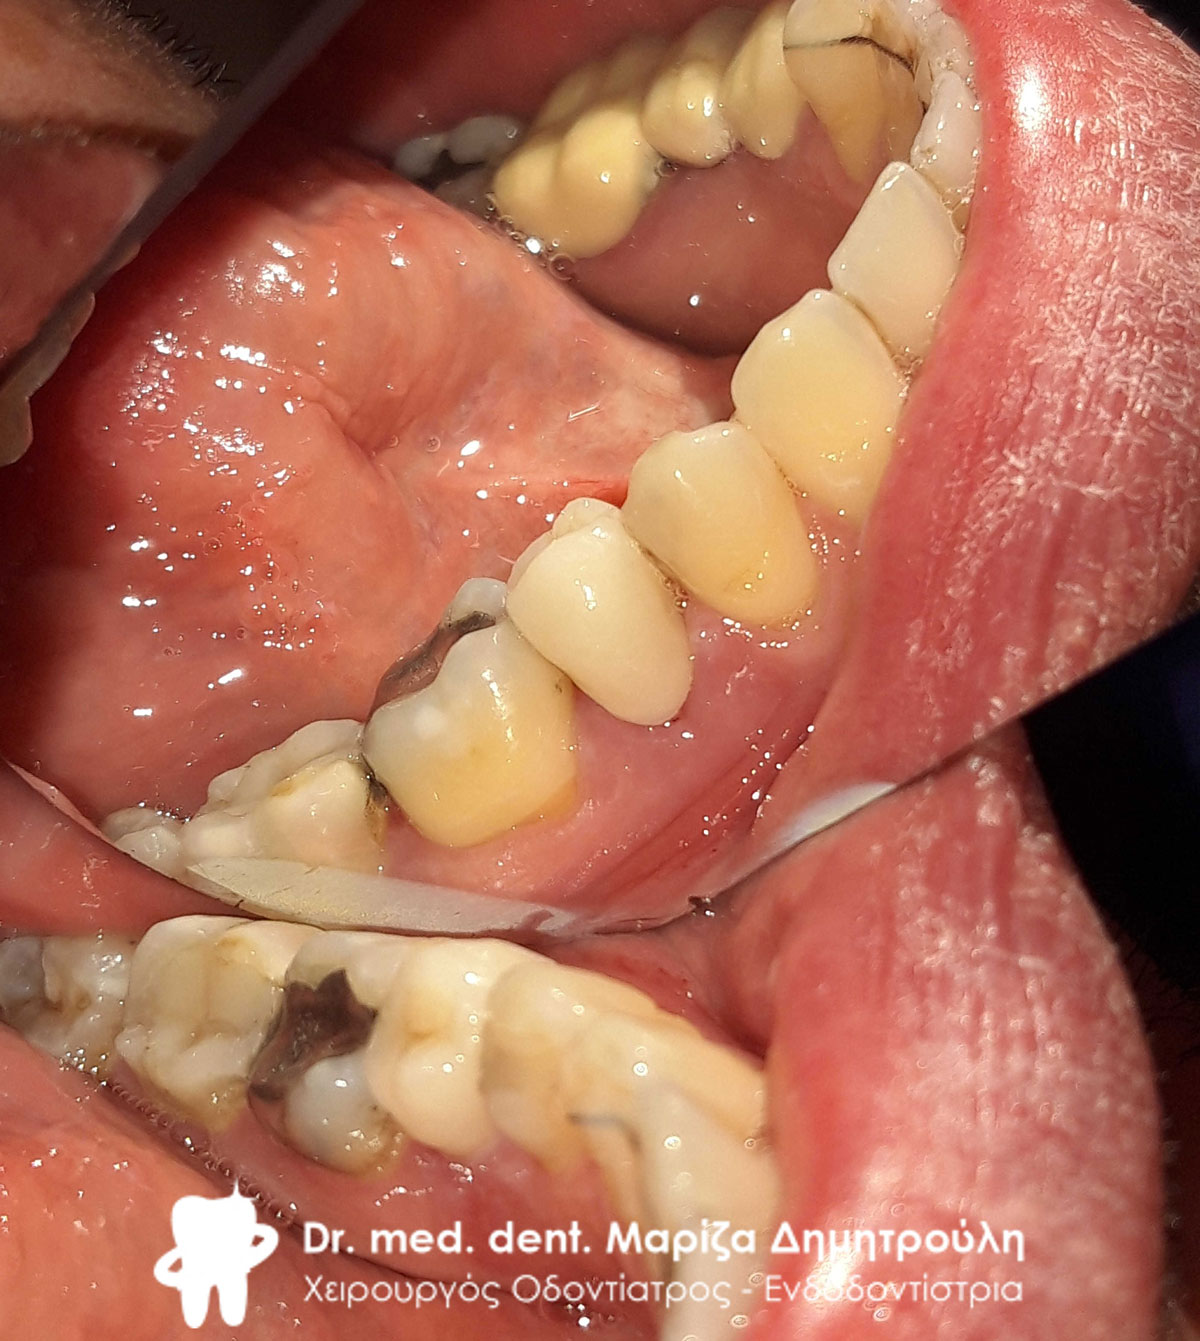

Περιστατικό – Ολοκεραμική στεφάνη / θήκη ζιρκονίου στην αριστερή πλευρά της κάτω γνάθου

Ο ασθενής είχε ένα παλιό μεγάλο σπασμένο σφράγισμα στον κάτω γομφίο. Το δόντι αρχικά απονευρώθηκε και στη συνέχεια καλύφθηκε με ολοκεραμική θήκη ζιρκονίου.

Αρχική κλινική εικόνα του δοντιού με το παλιό σπασμένο σφράγισμα

Κλινική εικόνα της ανασύστασης του δοντιού

Τελική εικόνα της ολοκεραμικής θήκης